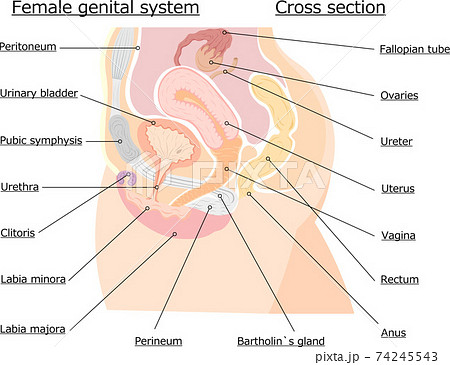

女性器の断面図 Listen さくやの囁き

子宮横からの断面図 名称付き メディカルイラスト図鑑 無料の医療 美容素材集

骨盤臓器脱 亀田メディカルセンター ウロギネ 女性排尿機能センター

女性骨盤内臓器 2分解モデル ボード型 日本スリービー サイエンティフィック

女性骨盤 内臓 骨盤底筋付 6分解モデル 日本スリービー サイエンティフィック

子宮 断面図 女性のからだのイラスト素材

骨盤 女性 解剖学 切断断面 卵巣 卵管 子宮 膀胱 膀胱 尿路 クリトリス 尿道 尿道括約筋 膣 外陰結腸 直腸括約筋が示される のイラスト素材

女性骨盤 内臓 骨盤底筋付 6分解モデル 日本スリービー サイエンティフィック